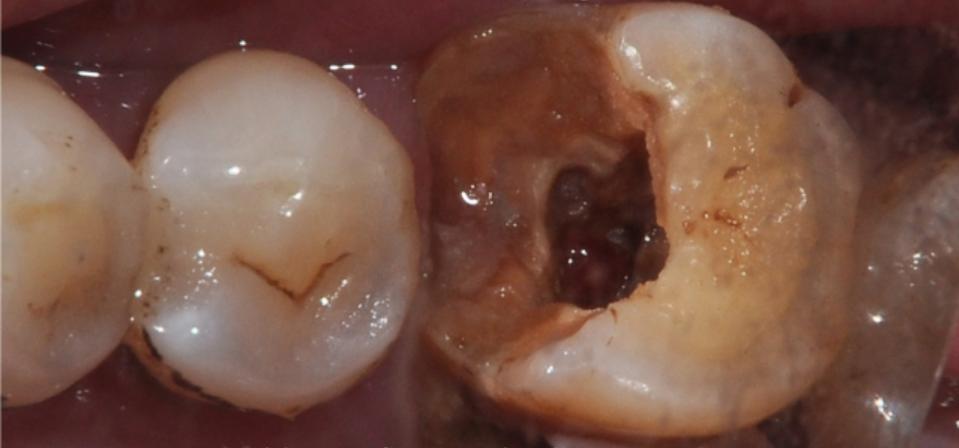

牙齿硬组织是由牙釉质、牙骨质和牙本质三部分构成的,内部的空腔称为髓腔。髓室底穿孔是由于龋坏、病理性吸收或牙髓治疗失误等原因造成的牙髓腔和牙周的病理性相通。髓室底就好比是一座房子的地基,髓室底穿孔了,就等于是地基漏了,危害可想而知。一旦髓室底穿孔了,穿孔地方的组织就可能引起炎症的反复发作,影响牙槽骨吸引,让患牙的正常功能难以发挥。如果不及时治疗,就会最终导致牙齿坏死、腐蚀、拔除。

比如,髓腔生理性的异常,或者髓腔随着年龄增加,造成髓室顶和髓室顶非常接近,再有就是由于龋病、创伤以及牙齿修复过程的损伤使得髓室发生病理性钙化,形成髓石,较多数的髓石与髓室底或侧壁粘连,就会让髓室解剖不清,形成髓室顶穿孔现象。

在临床中,大多数医生遇到髓室底穿孔的患者,一般会建议拔除患病牙齿,即便当时选择做了充填补牙的解决办法,但最终还是难以避免拔牙这样的结果。这主要还是因为髓室底位置较深,而且隐蔽,穿孔修复时对修补材料要求极高,而诊疗医生因为视野受限,治疗难度也会大大增加,治疗效果也难以达到满意。